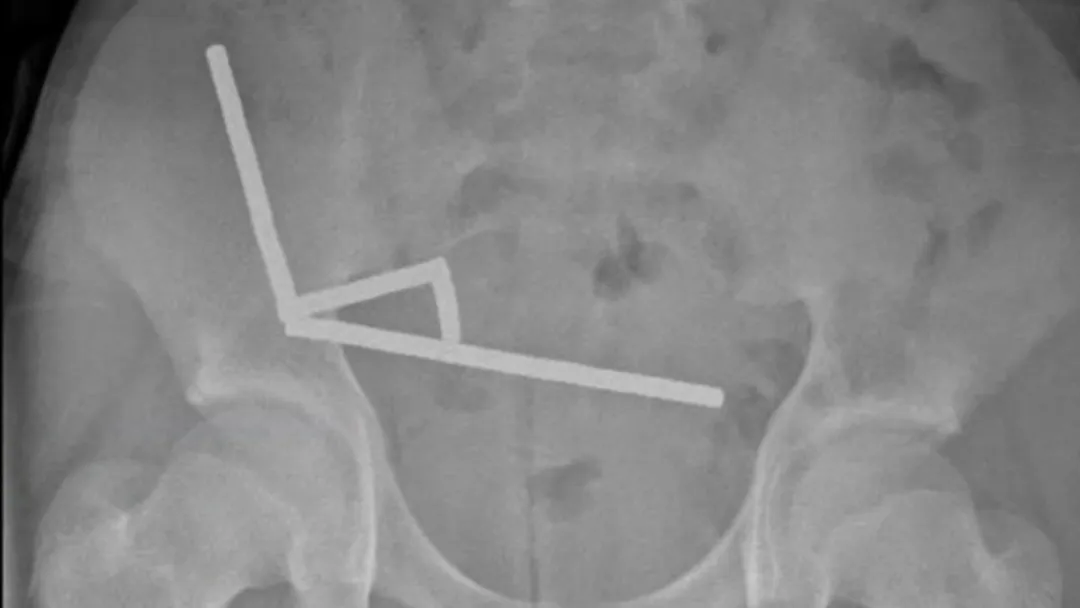

医生通过 X光片观察到,男孩肠道的不同部位出现了四条线状的磁铁链。

腹部 X光片显示了磁铁分布情况来源:Lekamalage et al.,NZMJ,2025

200颗磁铁在患儿腹中形成了磁铁链。来源:Lekamalage et al.,NZMJ,2025